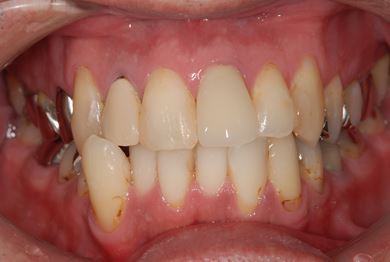

治療後

• 治療後